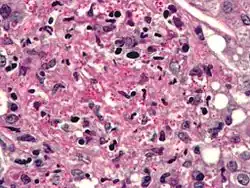

Histoplasmosis. PASD stain.

Histoplasma capsulatum can cause histoplasmosis in humans, dogs and cats. The fungus is most prevalent in the Americas, India and southeastern Asia. It is endemic in certain areas of the United States. Infection is usually due to inhaling contaminated air.